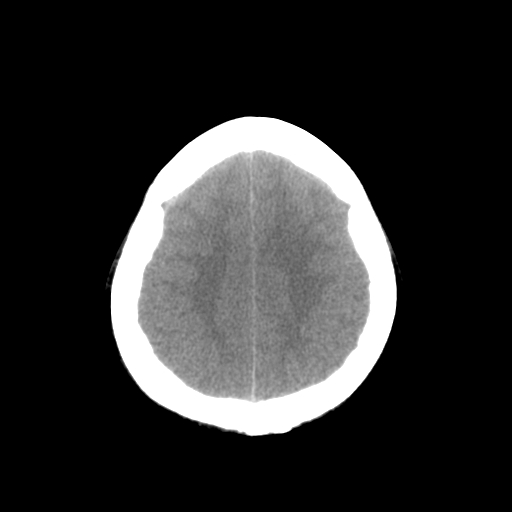

男,34岁,头痛数天。请大家看看是否有占位.

梗阻性脑积水,间质性脑肿胀,幕下占位可能,必须进一步检查。

右侧小脑半球占位压迫四脑室并幕上脑积水征像;建议增强或mr检查